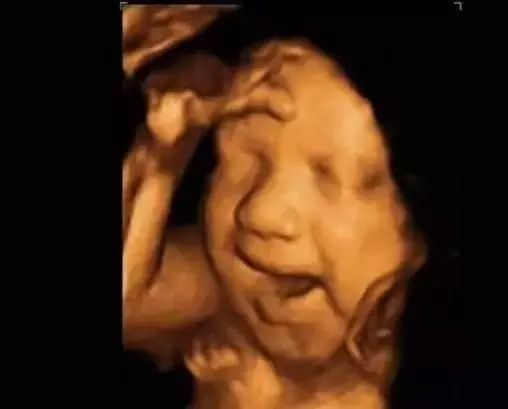

第三种:通过四维彩超图看清胎儿性别

孕后期宝宝已经很大了,占了整个显示器也不好看,孕中期最好看,我一共看到过3次,要在测量股骨(大腿骨)的时候看(省立一般是先测量胎心,然后是在显示器上拉个圆圈测量头围和双顶径,随后是拉条直线测量股骨)。

小提示,通过四维彩超看男女,最好是在怀孕15周之后。因为在怀孕12周之前,男宝和女宝的生殖器官看上去是一样的,是一点点小芽,12周之后开始了差异性的发育,女宝宝的小芽会分开往里面发育,而男宝宝的则开始变成像外突出发育为小JJ。而这一系列的发育,要到15周后才能通过四维彩超清晰的鉴别出来。所以通过四维彩超看性别,太早了是不行的。